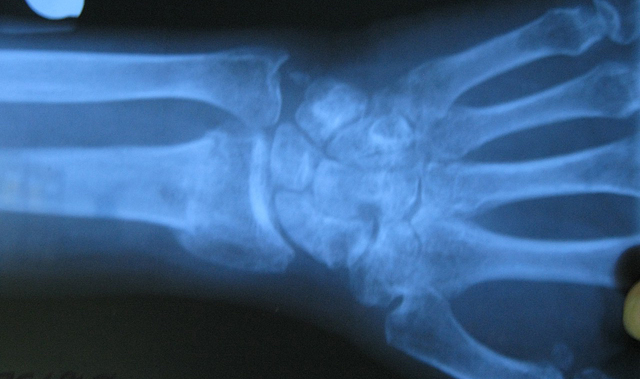

Врачи отмечают, что костная мозоль является важным этапом в процессе заживления переломов. Она формируется в результате регенерации костной ткани и служит для восстановления целостности кости. Однако, по мнению специалистов, существует тонкая грань между нормальным и патологическим процессом. В некоторых случаях костная мозоль может образовываться неправильно, что приводит к деформациям и функциональным нарушениям. Врачи подчеркивают, что важно внимательно следить за процессом заживления, особенно при сложных переломах или у пациентов с сопутствующими заболеваниями. Регулярные обследования и рентгенографические исследования помогают выявить возможные отклонения на ранних стадиях, что позволяет своевременно корректировать лечение и предотвращать осложнения. Таким образом, понимание нормальных и патологических изменений в костной мозоли является ключевым аспектом в травматологии и ортопедии.

Локализация и последовательность формирования костной мозоли происходит таким образом, что непосредственно между костными элементами не могут происходить репаративные процессы. Все возможно благодаря надкостнице. Поэтому сначала образуются признаки заживления перелома в поднадкостничных отделах кости, затем во внутреннем слое, возле костномозгового канала, и только после этого сращение происходит непосредственно между костными отломками. При этом она имеет вид беспорядочных наростов на поверхности кости, которые могут иметь самые разные размеры и распространенность. Со временем происходит их рассасывание с локализацией только в месте перелома. Больше всего заметна костная мозоль после перелома ключицы, что связано с непосредственным подкожным ее расположением.

На первом, который начинается после 7-9 дней посттравматического периода, образуется первичная мозоль. Она представлена соединительнотканными элементами. Если сказать об этом проще, то это обычный рубец, который бывает на любых тканях. Но в кости он претерпевает дальнейшие перестройки в виде преобразования в хрящевые элементы. Данные изменения длятся около месяца. Если в дальнейшем происходит отложение солей кальция, то хрящ превращаются в окостеневшие ткани. На это необходимо не менее 3 -5 месяцев. По своей плотности они похожи на плотную кость, но по морфологической структуре – совсем другие. Только по происшествие одного года возможно сказать об окончательном формировании костной мозоли.